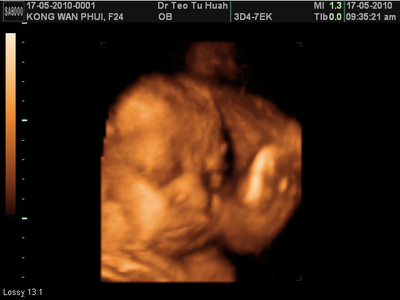

不知道baby到底幾時出世,現在心情基本上還不錯。

有時候想到baby出世那天,還是會有一點緊張的。

擔心到那一天的時候,情況很亂,然後不知道產程的時間長不長。

希望baby乖乖,不要讓mummy痛那麼久。